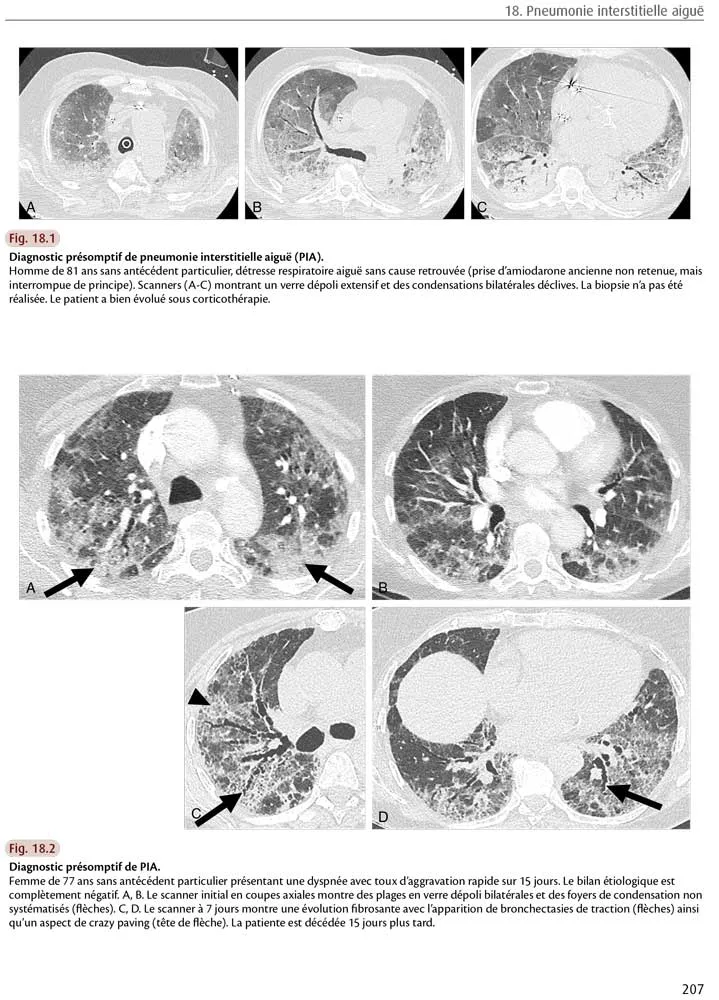

Les caractéristiques scanographiques de la PIA dérivent des lésions histologiques avec également des modifications au cours du temps. Initialement, le scanner montre des plages extensives bilatérales de verre dépoli situées dans des zones non déclives, des condensations dont la distribution évolue avec le temps : d’abord hétérogènes, patchy, elles évoluent progressivement vers des condensations gravito-dépendantes (fig. 18.1). Il s’y associe parfois du crazy paving avec une prédominance sous-pleurale. Plus tardivement, ces lésions laissent la place à des bronchectasies de traction, des opacités réticulaires, du rayon de miel et des signes de distorsion architecturale (fig. 18.2).

Fig 18.1 et 18.2